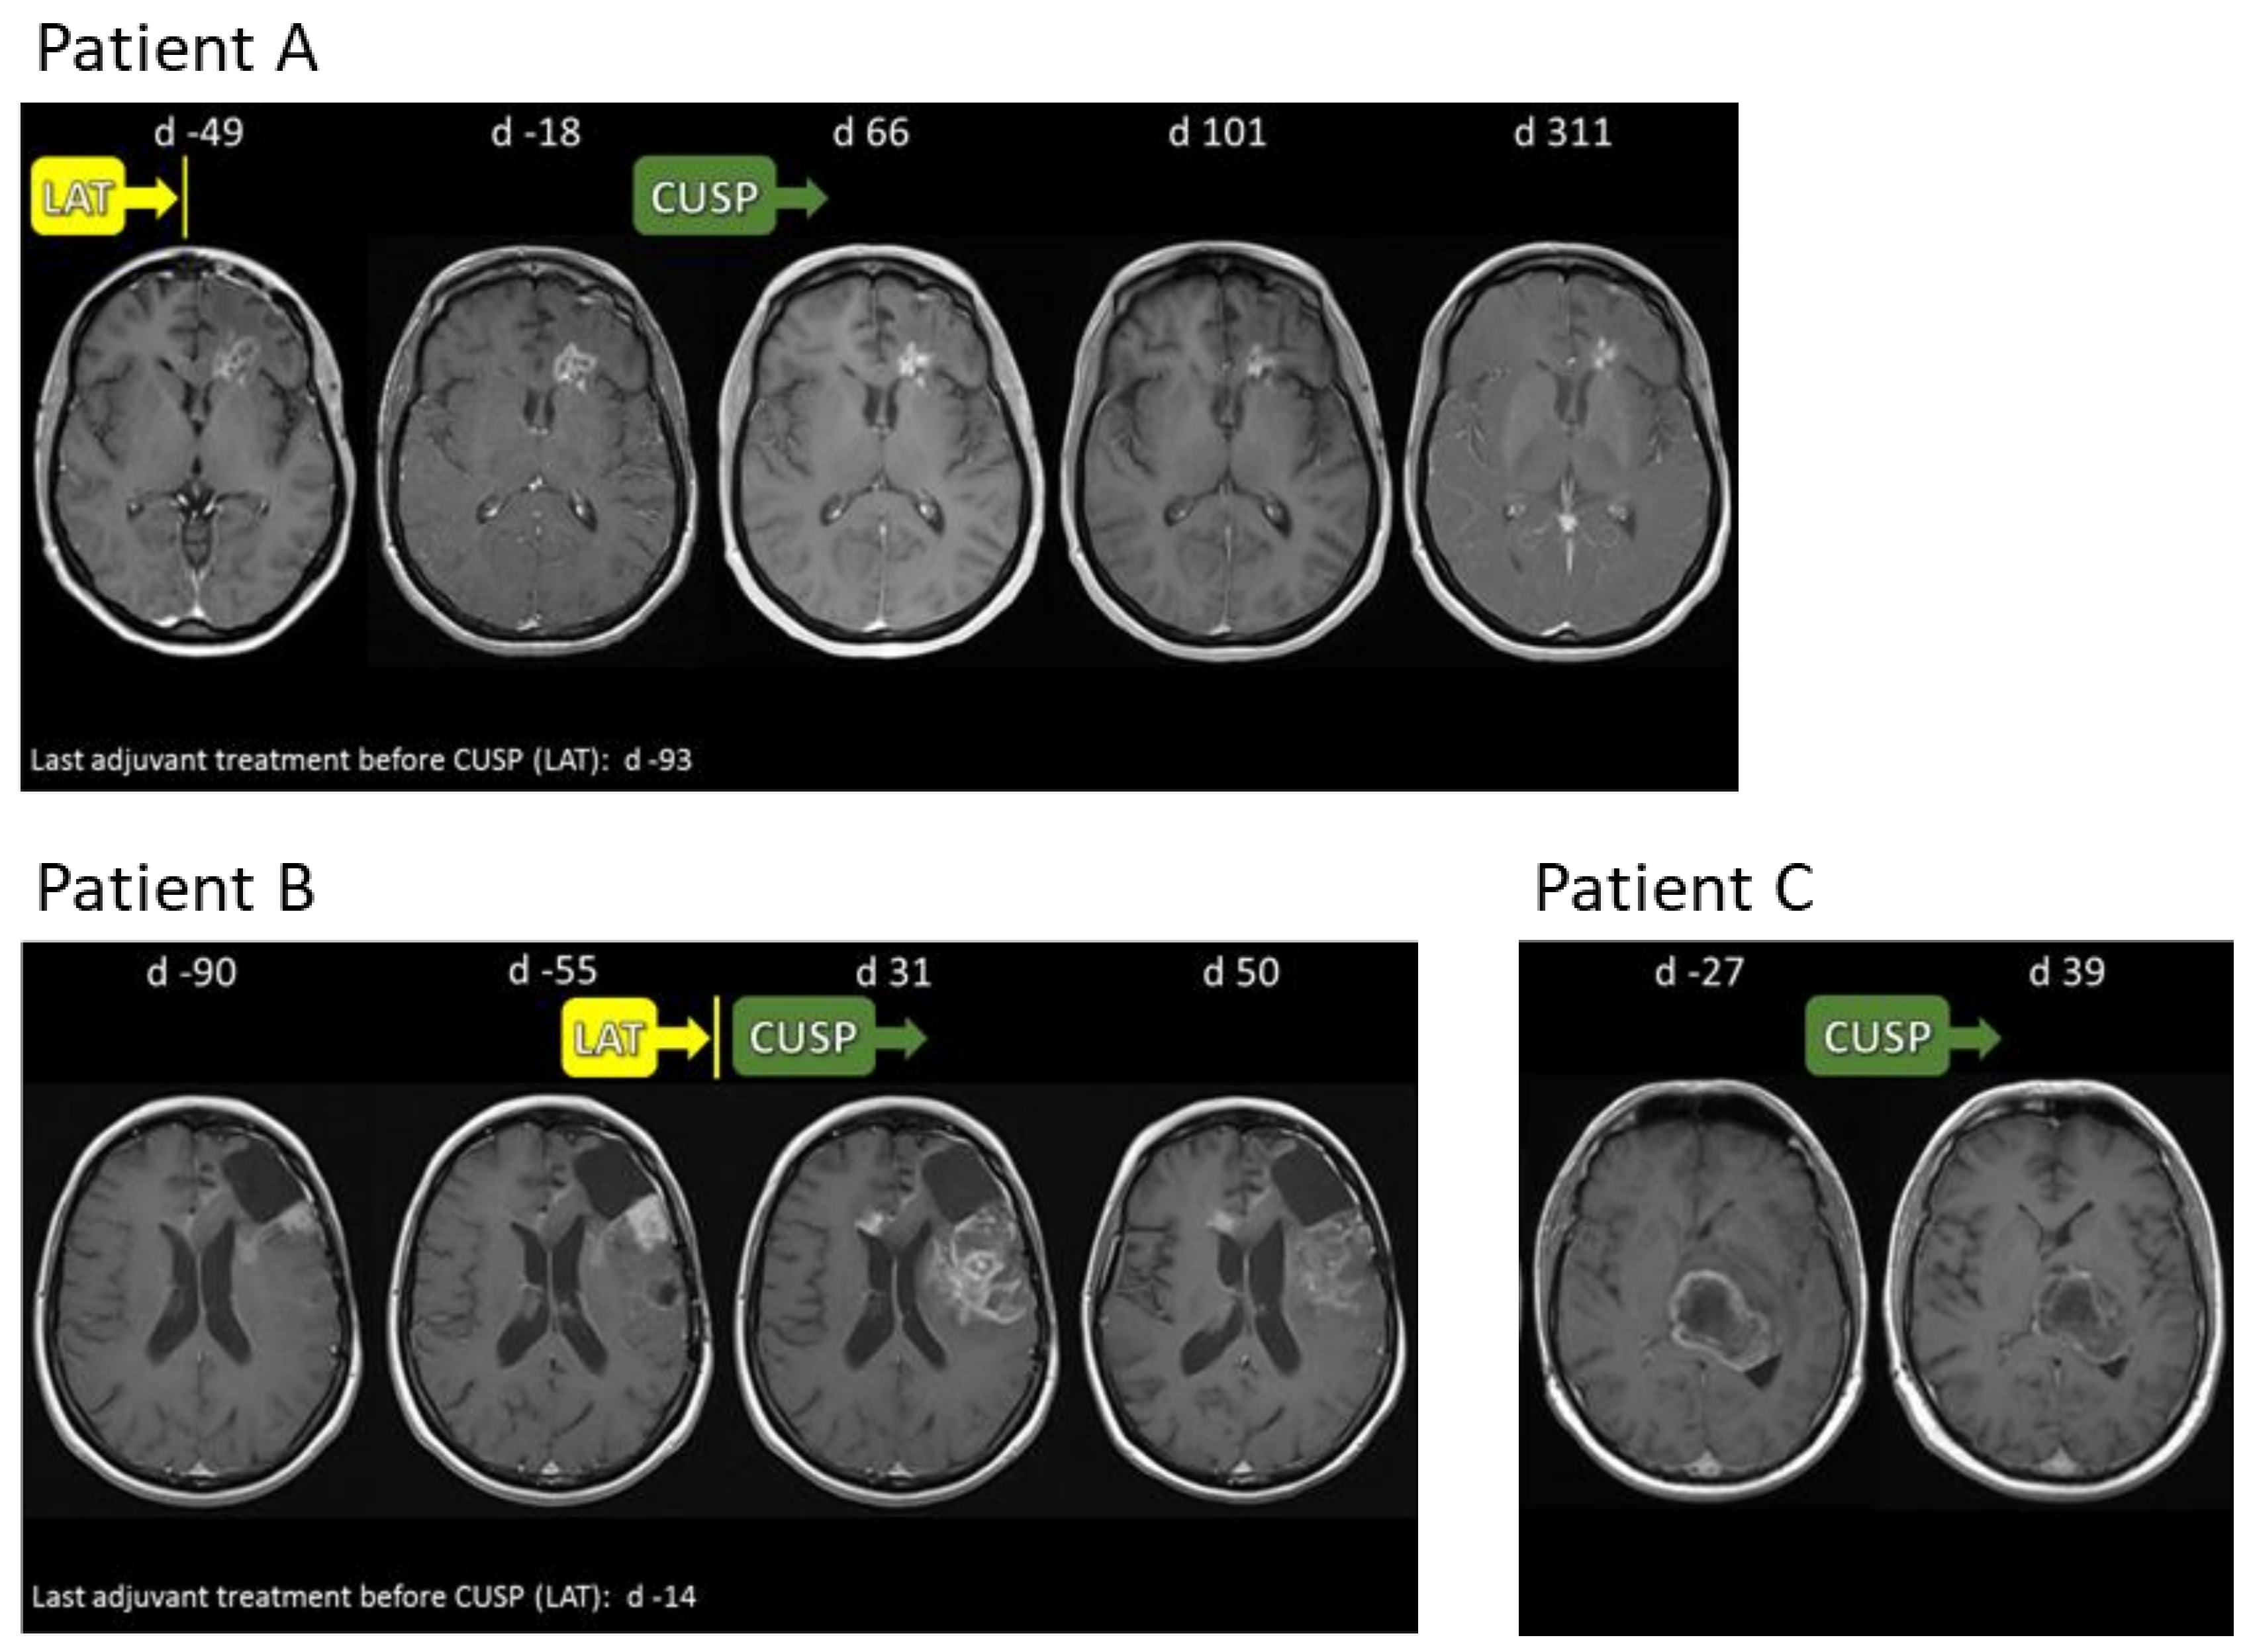

2.8. CUSP9v3 Affects Contrast Enhancement on Magnetic Resonance Imaging (MRI)